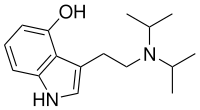

| 4-HO-DIPT | artificial | 4-OH | CH(CH3)2 | CH(CH3)2 | 4-hydroxy-N,N-diisopropyltryptamine | 132328-45-1 |